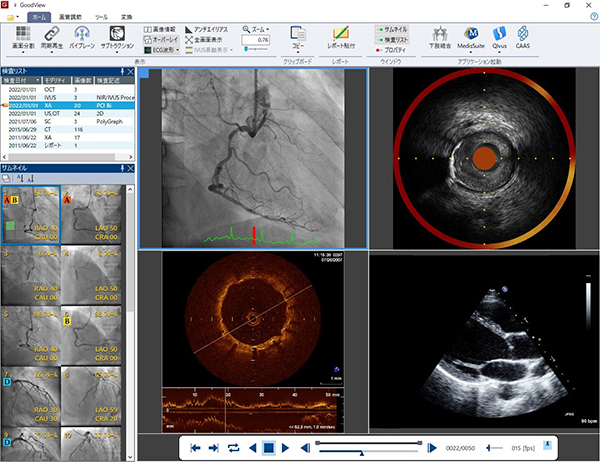

・DICOMビューワ「GoodView」シリーズ

GoodViewはシンプルなデザインかつ直感的な操作性を追求したDICOMビューワでありながら,IVUS像の長軸比較表示,簡易計測機能やファイルフォーマット変換機能など医療現場で求められる多くの声をカタチにした多機能ビューワです。Goodnetの標準ビューワとしてだけでなく単体ソフトウェア「GoodViewPRO(Windows対応単体ソフトウェア)」としても提供しております。